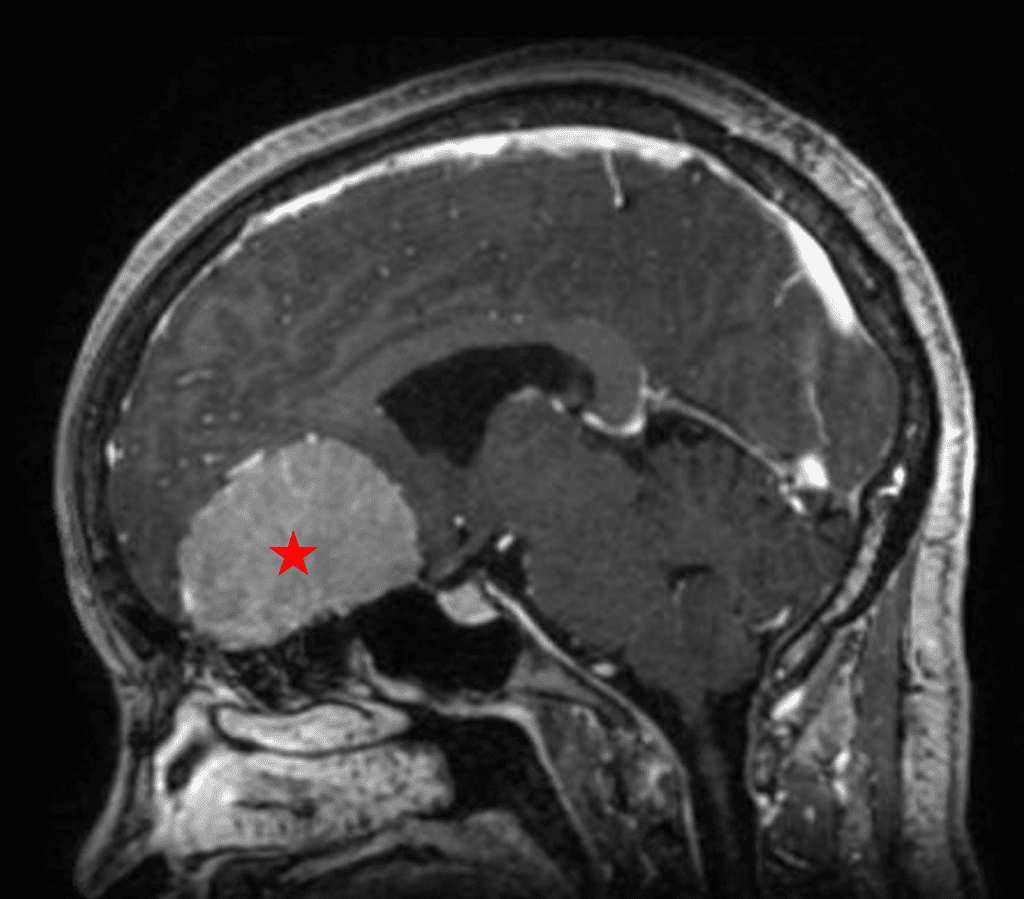

She was started on high-dose steroid and antiseizure prophylactic medicine. Surgical intervention was offered for mass effect, symptomatic relief, neurologic preservation, and histopathologic diagnosis. Dr. Gaudin performed a bifrontal craniotomy with complete resection of neoplasm through an interhemispheric and subfrontal approach. Postoperative imaging demonstrated a gross total resection without residual tumor and resolution of mass effect (Figure 1b and 2b). Intraoperative pathology was consistent with meningioma, WHO grade 1. She recovered very well, and was discharged home on postoperative day 3. On her follow-up outpatient visit, her preoperative symptoms had fully resolved, and her olfactory sense was maintained.

Figure 2b – Postoperative MRI demonstrating resolution of mass effect.